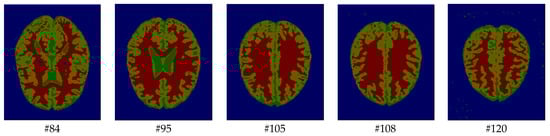

As mentioned before, the images of the first five datasets in Table 3 were used to evaluate the performance of the HMRF-WOA. Figure 1, Figure 2, Figure 3, Figure 4 and Figure 5 show some slices of a T1-weighted image (slices: 84, 95, 105, 108, 120). These brain images correspond to the slices under different types of conditions, such as database type, dimension image, noise level, intensity non-uniformity level, and slice thickness (mm). In Table 1, rows 1 to 5 summarize the parameters of Figure 1, Figure 2, Figure 3, Figure 4 and Figure 5, respectively. Figure 6 represents the ground truth segmentation of slices 84, 95, 105, 108, and 120. In this figure, each column contains the three tissues, GM, WM, and CSF, of each slice. Figure 7, Figure 8, Figure 9, Figure 10 and Figure 11 show the segmentation results, where the four tissues (BG, GM, WM, and CSF) are shown with different colors. The yellow, red, and green colors represent the segmented regions of GM, WM, and CSF, respectively. As we can also see from these figures, the resulting segmented images in Figure 7, Figure 8, Figure 9, Figure 10 and Figure 11 are almost close to the initial images in Figure 1, Figure 2, Figure 3, Figure 4 and Figure 5.

The qualitative analysis provides a visual representation of the segmentation approaches. The visual comparison of the resulting images using the HMRF-WOA appears to be more similar to the reference image (ground truth), where Figure 1, Figure 2, Figure 3, Figure 4 and Figure 5 show the GM, WM, and CSF tissue regions of the reference image with higher values of noise levels (3, 5, 7, and 9%) and intensity non-uniformity levels (20, 40%), whereas Figure 7, Figure 8, Figure 9, Figure 10 and Figure 11 show the subject images obtained using the proposed technique. However, this result shows that with higher values of noise and intensity non-uniformity, the algorithm, with its hyperparameters, is able to segment the tissue regions correctly.

Figure 9. Segmentation results of the images illustrated in Figure 3.